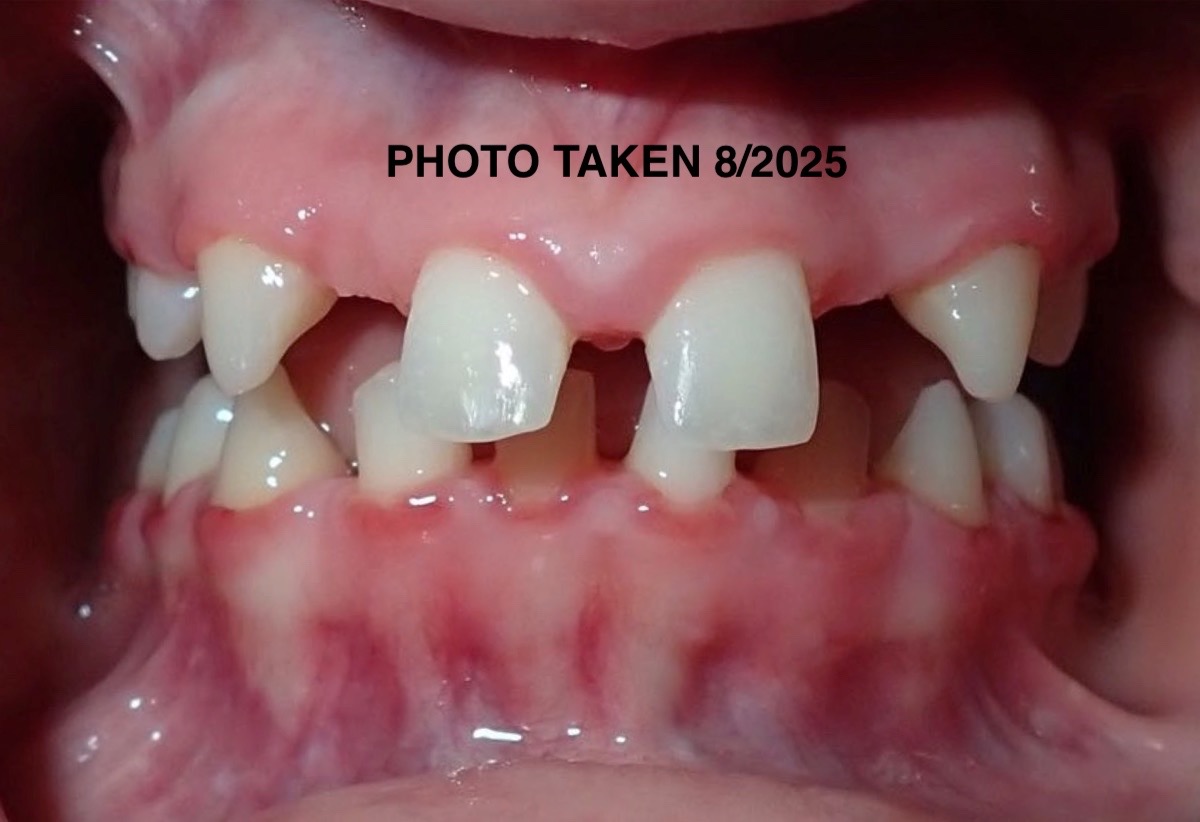

We were informed a few years ago that our daughter Laila is missing “14 permanent adult teeth” they just never came in. It is quite the anomaly and we are told by many specialists that she has a very unique situation and that this is not something that they have ever seen before or even see on a regular basis.

The diagnosis that they have so far given her is “Microdontia” a condition which the few teeth that did come in are abnormally small and not functional along with “Ogliodontia” being born without one or more permanent teeth (in her case 14 are missing). In conjunction with all the work that will need to be done to restore all of her teeth she will also be needing to undergo two extremely invasive surgical procedures, crown lengthening of the bone and enamel of her full mouth (removal of gums - scheduled in November 2025) and Mandibular advancement surgery a significant procedure where they will need to reconstruct her jaw due to certain abnormalities she was born with. There is also some speculation that she may possibly have a genetic disorder, called Pierre Robbin Sequence or Ehlos Danlos Syndrome and we are currently working with a Genetic Doctor to investigate all of this as well. The magnitude of all of this is daunting.

Nevertheless we have been navigating the beginning stages (PHASE 1) of what’s going to be many, many years of reconstruction and restoration of Laila’s mouth, jaw and teeth. The timeline was on a stand still for a while because they were waiting for her skull to fully develop so we are now at the point of being able to move forward. It is unfortunate to have to do all of this during her formative High School years but we just don’t have much of a choice and don’t want to prolong it as she has already been feeling the effects of not having a “normal” smile or a “functional” mouth to be able to chew food etc.

Laila is an extremely happy and positive young lady who doesn’t let any of these obstacles stop her from singing and performing on stage as her passion for Theater is strong! We hope to help her through this difficult journey with as much ease as possible so that she is able to continue her passions with grace but we are just not able to do it alone. Having a functional mouth (teeth/jaw) is so important for eating, speaking, singing and just quality of life, and the depth of this is immense and the end goal feels very lost to us right now.

Laila is truly dedicated to her future, our hope and wish for her is that she can feel good about herself as she continues to go through her young life and know that she doesn’t look strange or different and that she is able to have a normal and functional mouth/jaw/teeth someday when this is all said and done so that she is able to confidently shine her smile brightly on and off stage and have this all behind her while she is going through life. We just want her to be able to chew her food without any risk of choking or having to spit her food out while she is eating, the constant and painful locking of her jaw and severe migraines which all happens on a daily basis right now for her and that she will be able to have a future that doesn’t entail more than she’s already going to have to endure medically.